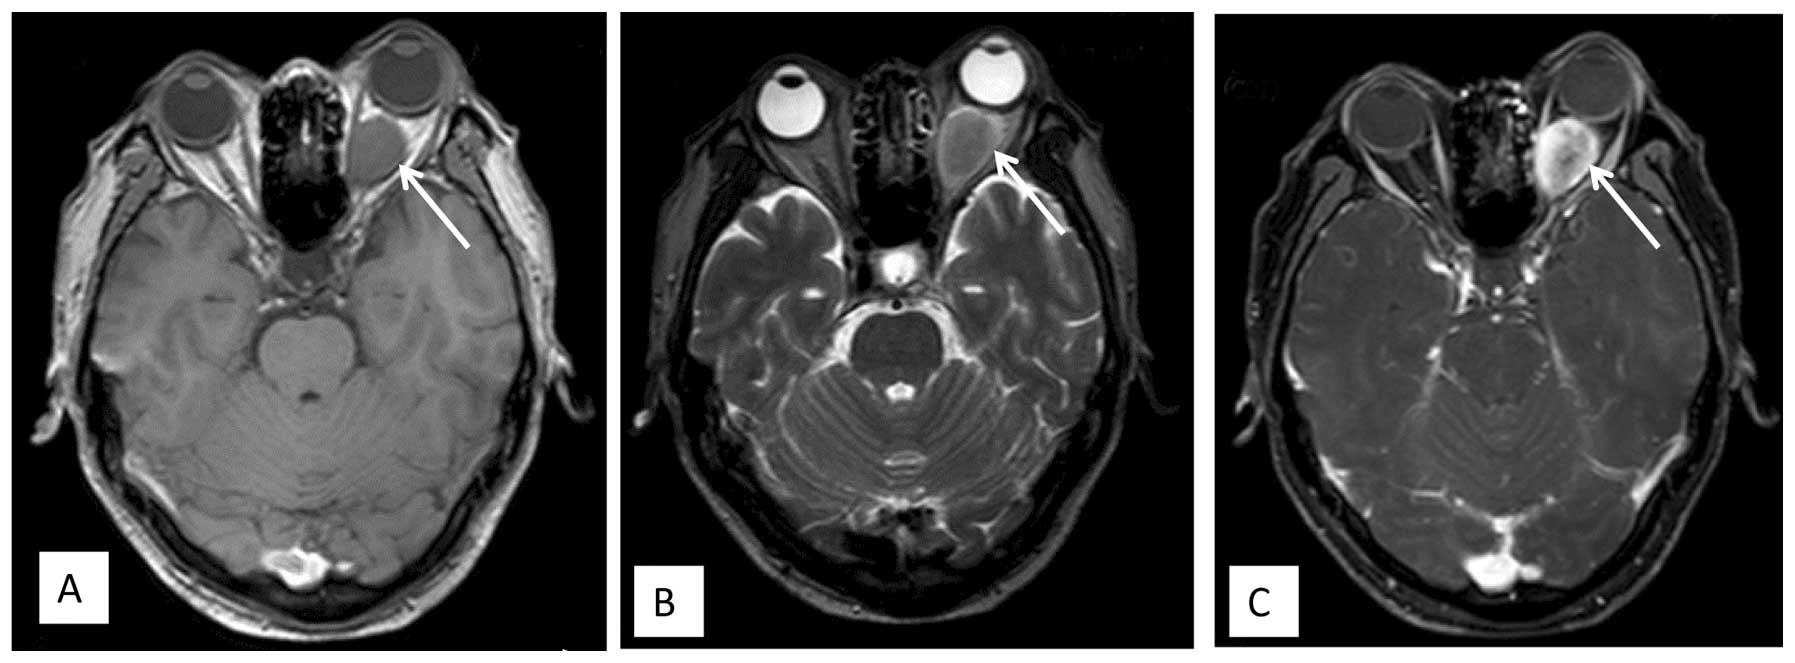

A 53-year-old male presented with a slowly enlarging mass in the right thigh in May 2008. The patient underwent a local excision at Shanghai General Hospital (Shanghai, China). and the histology revealed a diagnosis of MLPS. The patient subsequently received adjuvant radiotherapy (details unknown) and was free from recurrence for 34 months after the resection. The patient presented to The Sixth People's Hospital of Shanghai Jiao Tong University (Shanghai, China) on April 26, 2011, with lower back pain that radiated to the bilateral thighs for more than one month. Bone scans showed no evidence of bone metastasis. However, MRI showed abnormal signals in the vertebral body of T11 and T12, and a mass in the epidural region at the T11 and T12 vertebral level (Fig. 1). Angiography showed that the feeding vessels were the T11 and T12 intercostal arteries. Transcatheter arterial embolization was performed using polyvinylpyrrolidone and gelfoam particles, and the contrast extravasation almost disappeared in the two arteries. Next day, a laminectomy was performed and the soft tumor in the epidural region was marginally resected. Immunohistochemically, the tumor cells were positive for vimentin, slightly positive for Ki-67 (2%), and negative for cluster of differentiation (CD)31, CD34, S-100, smooth muscle actin, glial fibrillary acidic protein and CD56. These findings together with hematoxylin and eosin staining revealed a diagnosis of metastatic MLPS for the involved bones and the mass in the epidural region.

Figure 1.

(A) Sagittal T1-weighted image prior to gadolinium infusion showing hypointense signals in the spinous process of the T11 vertebra and an epidural mass with hypointense signals at the T11 and T12 vertebral level. (B) Sagittal T2-weighted, fat suppressive magnetic resonance imaging revealing hyperintense signals in the spinous process of the T11 vertebra and an epidural mass with hyperintense signals at the T11 and T12 vertebral level. (C) Well-enhanced mass following gadolinium-DTPA infusion and compression of the thoracic spinal cord.